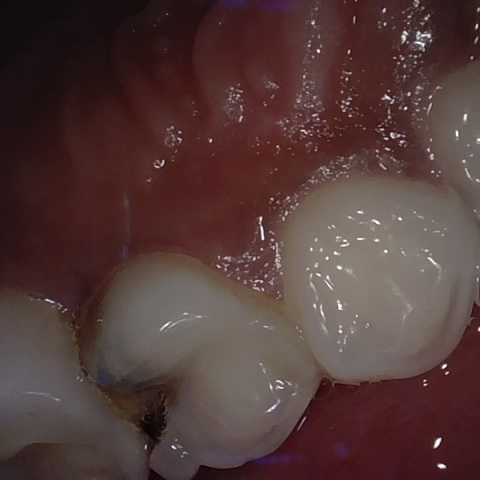

Annotated as "Good"